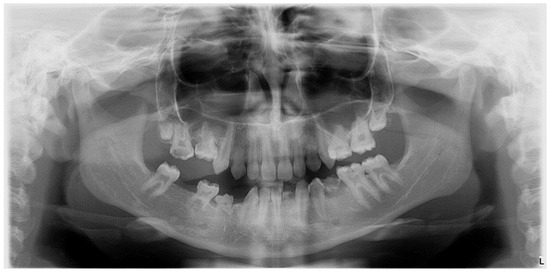

The prevalence of tooth number anomalies (such as agenesia and supernumerary teeth) among the 57 patients was 29.9%, with 82.4% (14 cases) of these anomalies being associated with MIH (molar-incisor hypomineralization). Only 17.6% (3 cases) of the tooth number anomalies were identified in the control group, and the difference was statistically significant, with a p-value of 0.009 (Figure 6)

Figure 6.

Graphic illustration of agenesis in the study group compared to the control group.

In the control group, two of the three cases of numerical anomalies were identified as supernumerary teeth, while one case was a secondary lower premolar hypodontia found among the 14 total cases of hypodontia.